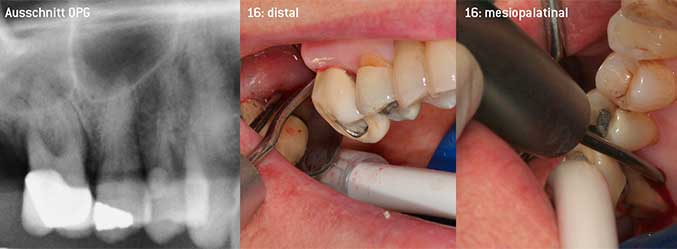

Als Initiatoren zur Entwicklung der neuen diamantierten Luftscaler-Spitze 3AP sahen es beide Zahnärzte als notwendig an, die Einschränkung in der Handhabung bisher kommerziell vermarkteter diamantierter Spitzen insbesondere während der Furkationstherapie oder in engen Knochentaschen zu verbessern. Dies sollte unabhängig von nicht-chirurgischem (Abbildung 2) oder chirurgischem Vorgehen sein (Abbildung 3).

(Fotos Abb 2 -4: © Dr. Chr. Graetz)

Das Ziel bestand darin, eine universell einsetzbare Spitze zu entwickeln, um zeitraubende Spitzenwechsel zu vermeiden. Daneben sollte aber die Anwendung der neuen Arbeitsspitzen sowohl in engen Knochentaschen von distal als auch am distalen Furkationseingang von Oberkiefermolaren einfacher sein und infolgedessen eine effektivere Instrumentierung ermöglichen. Dies wurde durch einen größeren Durchmesser des Instrumentenbogens (Abbildung 1) erreicht, was gerade bei Zähnen mit fortgeschrittenem Attachmentverlust und Furkationsbeteiligung von großem Vorteil während des geschlossenen Debridements ist (Abbildung 4).